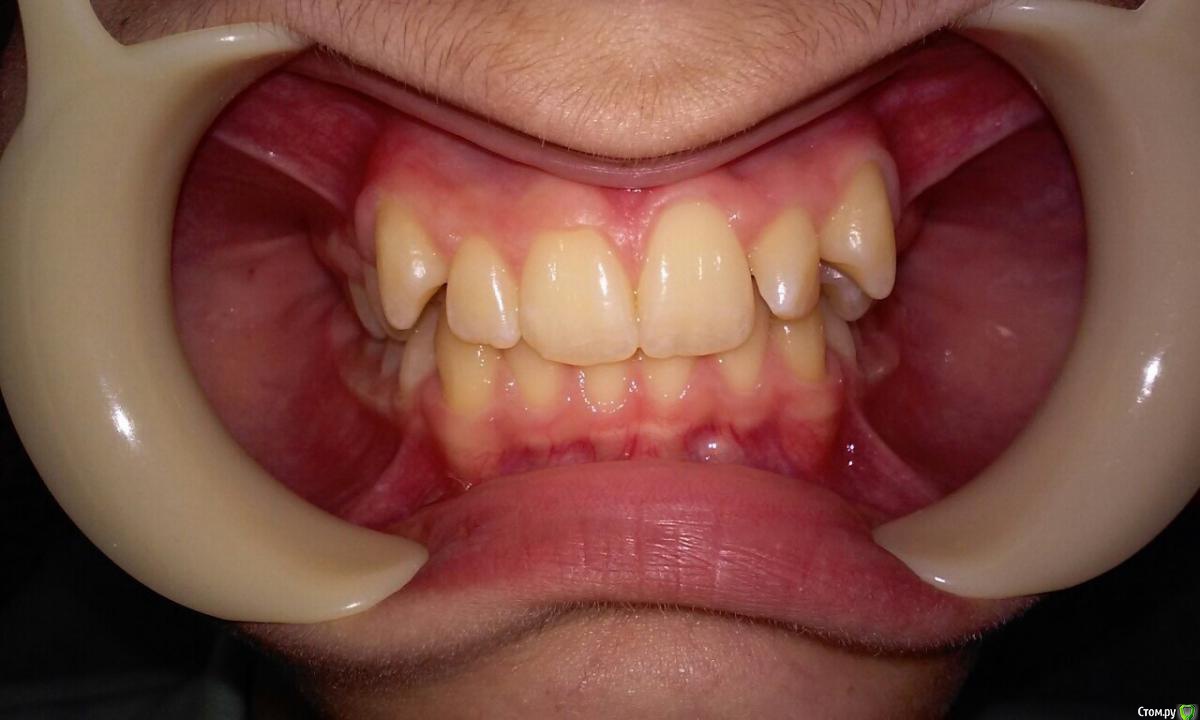

natkoorth1991 Опубликовано 28 августа, 2015 Поделиться Опубликовано 28 августа, 2015 мальчик, 13 лет, премоляры удалять не хотели, поставила хайракс на в / ч- получила перекрестную окклюзию. Извините за плохие фото( Что теперь делать? фото после: Ссылка на комментарий

Molox Опубликовано 29 августа, 2015 Поделиться Опубликовано 29 августа, 2015 Выведете. Наверх поставьте зауженную дугу, на низ - стандартную или широкую. Поскольку диастемы не появилось, у меня стойкое подозрение, что расширение было зубоальвеолярным, значит на брекетах вернуть все можно. Скажите, а зачем вообще аппарат ставили? Дефицит места минимальный, десна хорошая; на брекетах за 6 мес все бы расправилось. Ссылка на комментарий

Maverick Опубликовано 29 августа, 2015 Поделиться Опубликовано 29 августа, 2015 Хайрекс был не по показаниям. Обычная брекет система с этим справилась бы прекрасно. Снимайте его. Пока костная мазоль не образовалась переживать не надо, а это обычно занимает 4-5 месяцев, сняв аппарат получите рецидив и все вернется на круги своя. Либо как предложили выше скручивайте назад такими же темпами. Брекеты не ставьте пока не получить изначальную форму дуги, ну или близкую к ней. Трг это конечно хорошо, но надо смотреть на профиль - это показатель лечения, слепо доверять цифрам не совсем хорошая идея. Лечим не цифры, а людей. 2 1 Ссылка на комментарий